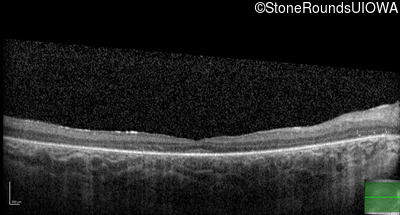

Age at visit: 10 years

Age at visit: 11 years

Age at visit: 12 years

Age at visit: 13 years

Age at visit: 14 years

Age at visit: 16 years